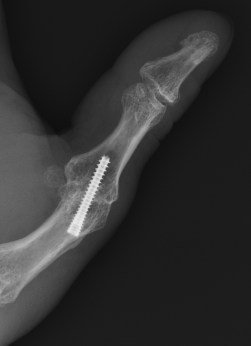

MCPJ fusion

![]()